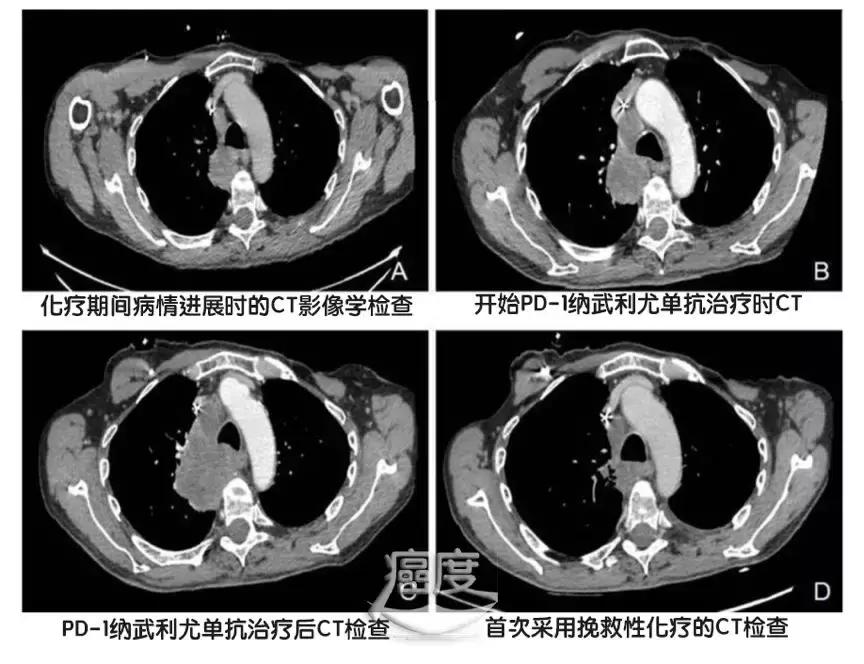

2017年8月,也就是传统治疗停止之后的2个月,开始使用PD-1的纳武利尤单抗,每15天一个疗程,使用的剂量为每公斤体重3毫克。2个月后,也就是4个治疗周期之后病情进展,PD-1看起来没有起到效果。

2017年11月,每周一次单药的紫杉醇治疗,2个月之后出现显著的疗效,病灶缩小,临床评估部分缓解(PR)。